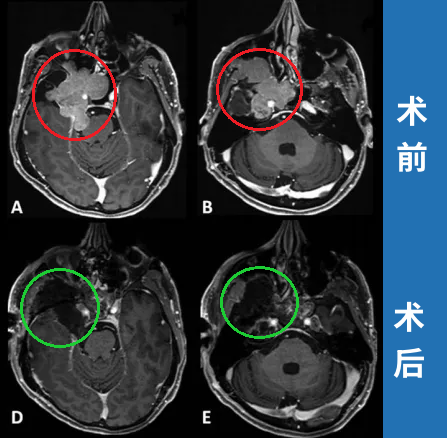

2012年,53岁的Leo突然发现自己嗅觉减退、视力下降时,就医检查发现右侧梅克尔腔脑膜瘤,随即进行了手术。谁能想到7年过后,脑膜瘤再次卷土重来,出现严重的V1(嗅神经)、V2(视神经)和V3(动眼神经)感觉减退和疼痛,症状比第一次手术前还要严重。磁共振成像(MRI)显示肿瘤大面积复发,延伸至海绵窦(CS)、后颅窝(PF)、蝶窦(SS)、翼腭窝(PPF)和颞下窝(ITF)。这个张牙舞爪的肿瘤,属实不太容易切除。

患者术前影像。(A)术前轴位T1加权钆增强磁共振成像(MRI),显示脑膜瘤延伸至后颅窝、海绵窦、眼眶和蝶窦。(B)肿瘤延伸至中颅窝、翼腭窝和颞下窝。(C)术前轴位计算机断层扫描(CT)显示蝶骨大翼侵蚀和蝶窦受累。

最终,手术顺利完成,根据术前术后影像对比,患者肿瘤得到完全切除。